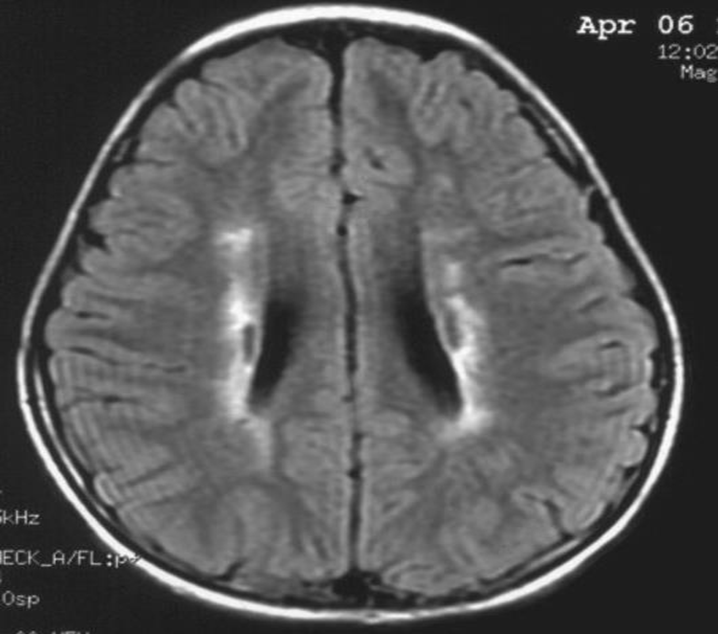

患者:林某某性別:男年齡:8 歲基本情況:出生后3個月臨床和頭部CT檢查診斷為腦癱。8年來病人曾在全國各地接受各種中西醫(yī)治療,病人入院時確診為痙攣性腦癱。治療時間:2005年7月接受干細胞移植手術。